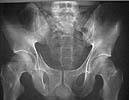

A 28 year old male jumped from the 4th floor on 11-25-2000 sustaining an L1 burst fracture that has been fixed anteriorly by the neurosurgeon with a strut between T12 and L2. A Kaneda device was placed anteriorly as well. My concern is the pelvic ring injury. There are bilateral sacral fractures through the foramen and a transverse element through the sacrum between S2 and S3. the lower part of the sacrum is displaced forward. Anteriorly there are right superior and inferior pubic rami fractures.

AP Pelvis